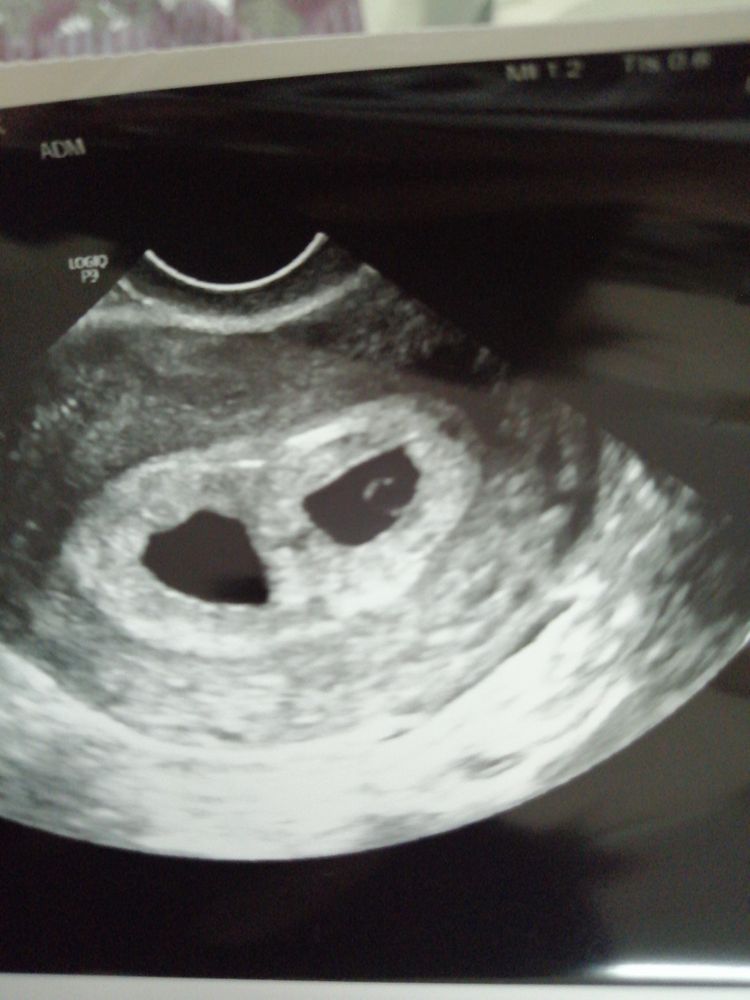

Изображение

Natali, по узи 5 недель акушерских

Поздравляю вас 🥳 А почему в желтом кружечке только 1 малыш, двойню же ждёте?😊

Alice, исправила))))